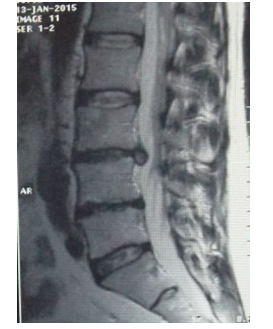

Patient C, 31 years old. Has acted with complaints on sharp pains in a loin, pulling pains in the left leg, numbness of the left leg, paresthesia. When examining antalgic scoliosis to the left, weakness in the right n / extremity, it’s shortening by 1.5cm, with Lassega s sharply positive on the right. MRI (ris.5-6) Disc L 4-5: moderate decrease in disc height and intensity MR - signal. Op. posterior median disc hernia with left lateralization of 17* 7.9* 7.9mm, with a tendency to sequestration (Figures 3A & 3B).

Figure 3 Patient C, before treatment.